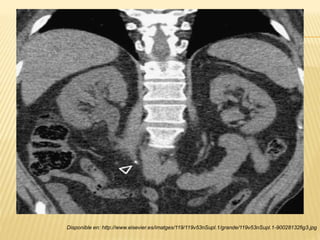

“TOMOGRAFÍA COMPUTARIZADA”

 Visualización del riñón y las vías de excreción

(uréteres) en un plano coronal.

 Estructuras peritoneales y retroperitoneales.

 Pacientes con cólico renal agudo.

 Sin contraste intravenoso.

 Distinguir cálculos uretrales distales de

“flebolitos”

Smith y Tanagho, "Urología general", Ed. Mc Graw Hill, ed. 18a, impreso cd. de México, 2008, pág. 265

Disponible en: http://www.elsevier.es/imatges/119/119v53nSupl.1/grande/119v53nSupl.1-90028132fig3.jpg